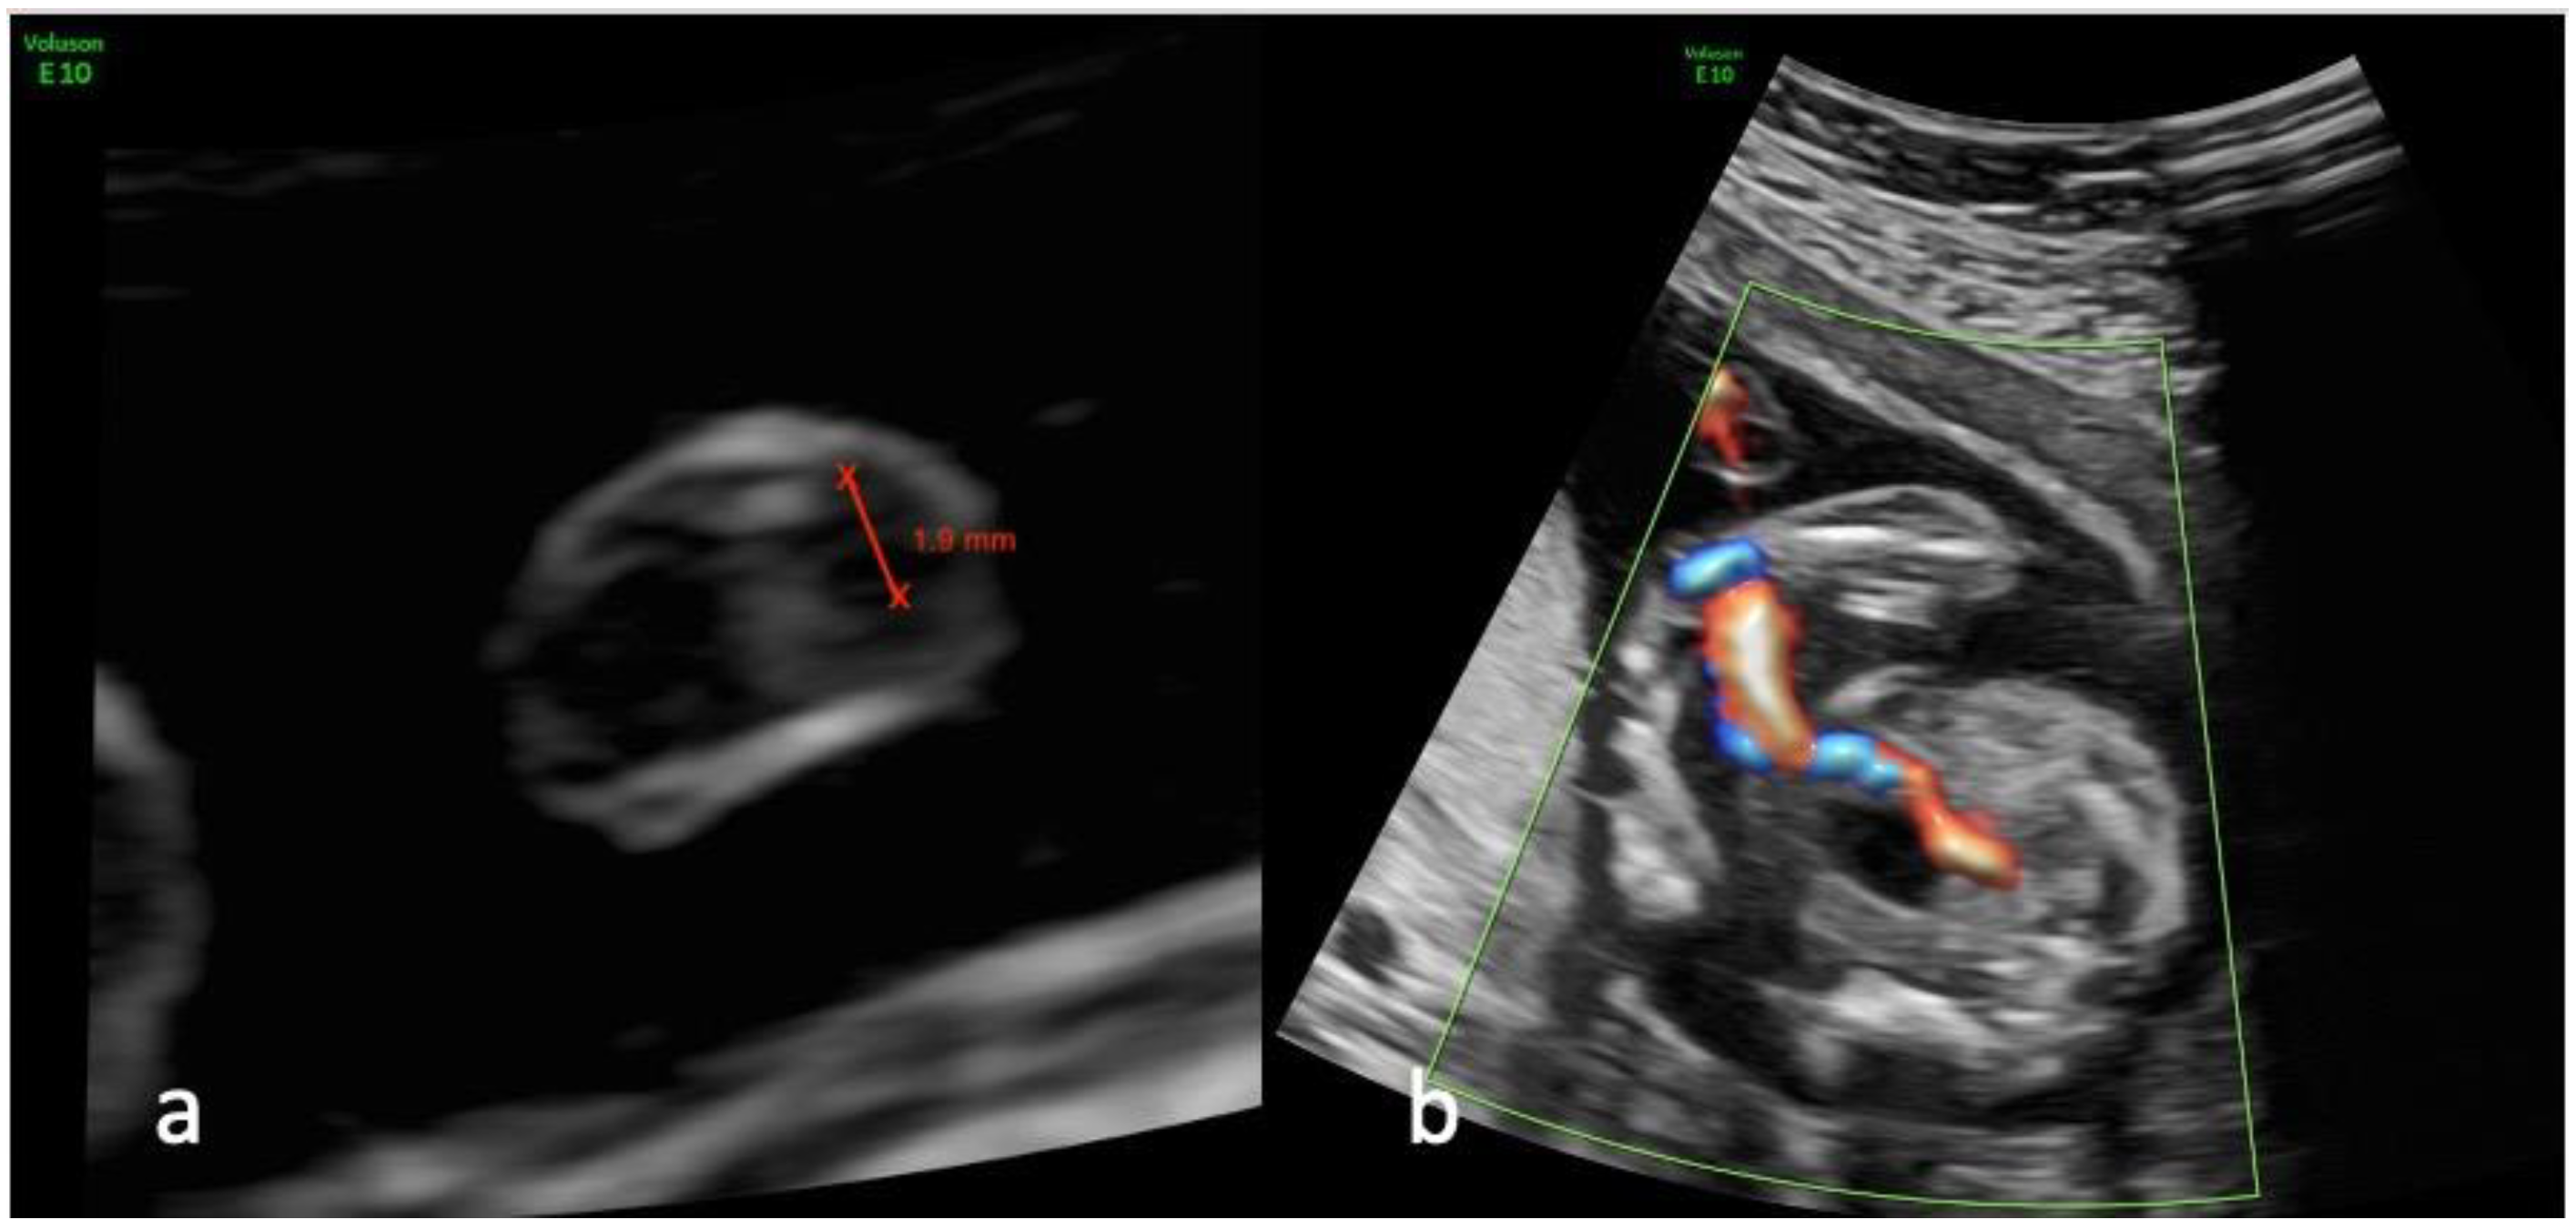

Figure 1.

Ultrasound views of the umbilical cord and its insertion at the level of the bladder in a fetus presenting a single umbilical artery at 20 weeks of gestation; (a) transverse view of a free loop of umbilical cord showing the measurement of the remaining artery; (b) color Doppler imaging mapping the insertion of the umbilical cord at the level of the bladder.